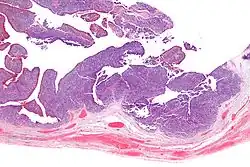

| Micrograph of transitional cell carcinoma of the ovary. H&E stain. |

Transitional cell carcinoma of the ovary (TCC of the ovary) is a rare type of ovarian cancer that has an appearance similar to urothelial carcinoma (also known as transitional cell carcinoma).[1]

TCC of the ovary is diagnosed by examination of the tissue by a pathologist. It has a characteristic appearance under the microscope and distinctive pattern of immunostaining.[2]

It is not related urothelial carcinoma.[1] It is in the transitional cell category of ovarian tumours which also includes malignant Brenner tumour and benign Brenner tumour.